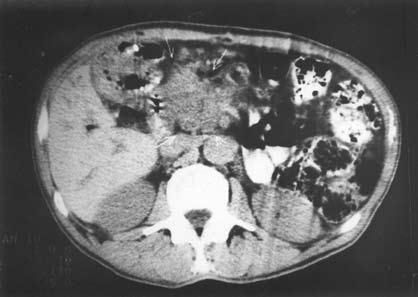

Компьютерная томография (КТ) является рентгенологическим методом высокой разрешающей способности, достаточно широко используемым при исследовании ПЖ. В принципе метод позволяет получить данные, аналогичные УЗИ, однако в ряде случаев дает возможность уточнить последние, например, при ожирении больного, наличии метеоризма, преимущественной локализации изменений в области хвоста железы (рис. 140).

В норме поджелудочная железа определяется на компьютерных томограммах в виде относительно гомогенного образования S‑образной формы. Признаками поражения железы являются неоднородность ее тени с участками уплотнения и разряжения, расширения, сужения и деформации протоков, одиночные или множественные полостные жидкостные образования. Для ложной кисты, как и при УЗИ, характерно наличие капсулы и однородное или неоднородное (при наличии в полости секвестров или замазкообразного детрита) содержимое. Высока разрешающая способность КТ при наличии в железе обызвествлений и протоковых конкрементов. Злокачественные новообразования выглядят при КТ очагами, плотность которых ниже плотности железы.

Рис. 140. КТ при хроническом кальцифицирующем панкреатите. На снимке видны кисты головки ПЖ, расширенный ГПП и кальцинат в его просвете.